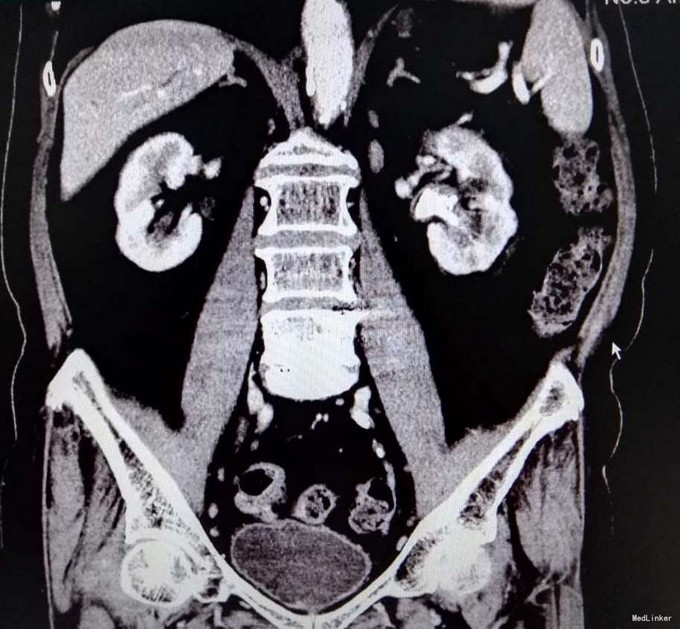

3、查体:未发现明显阳性体征 4、辅助检查:双肾CTU:1、左肾多发结石,左侧肾盂输尿管炎症,左侧双J管置入术后改变,2、双肾多发囊肿,

5、诊断:肾积水伴输尿管结石 6、治疗:入院后完善相关检查,ctu如上述,排除手术禁忌症后行输尿管软镜下碎石取石术,术程顺利,术后给予抗炎、补液等处理,术后恢复良好,予以出院